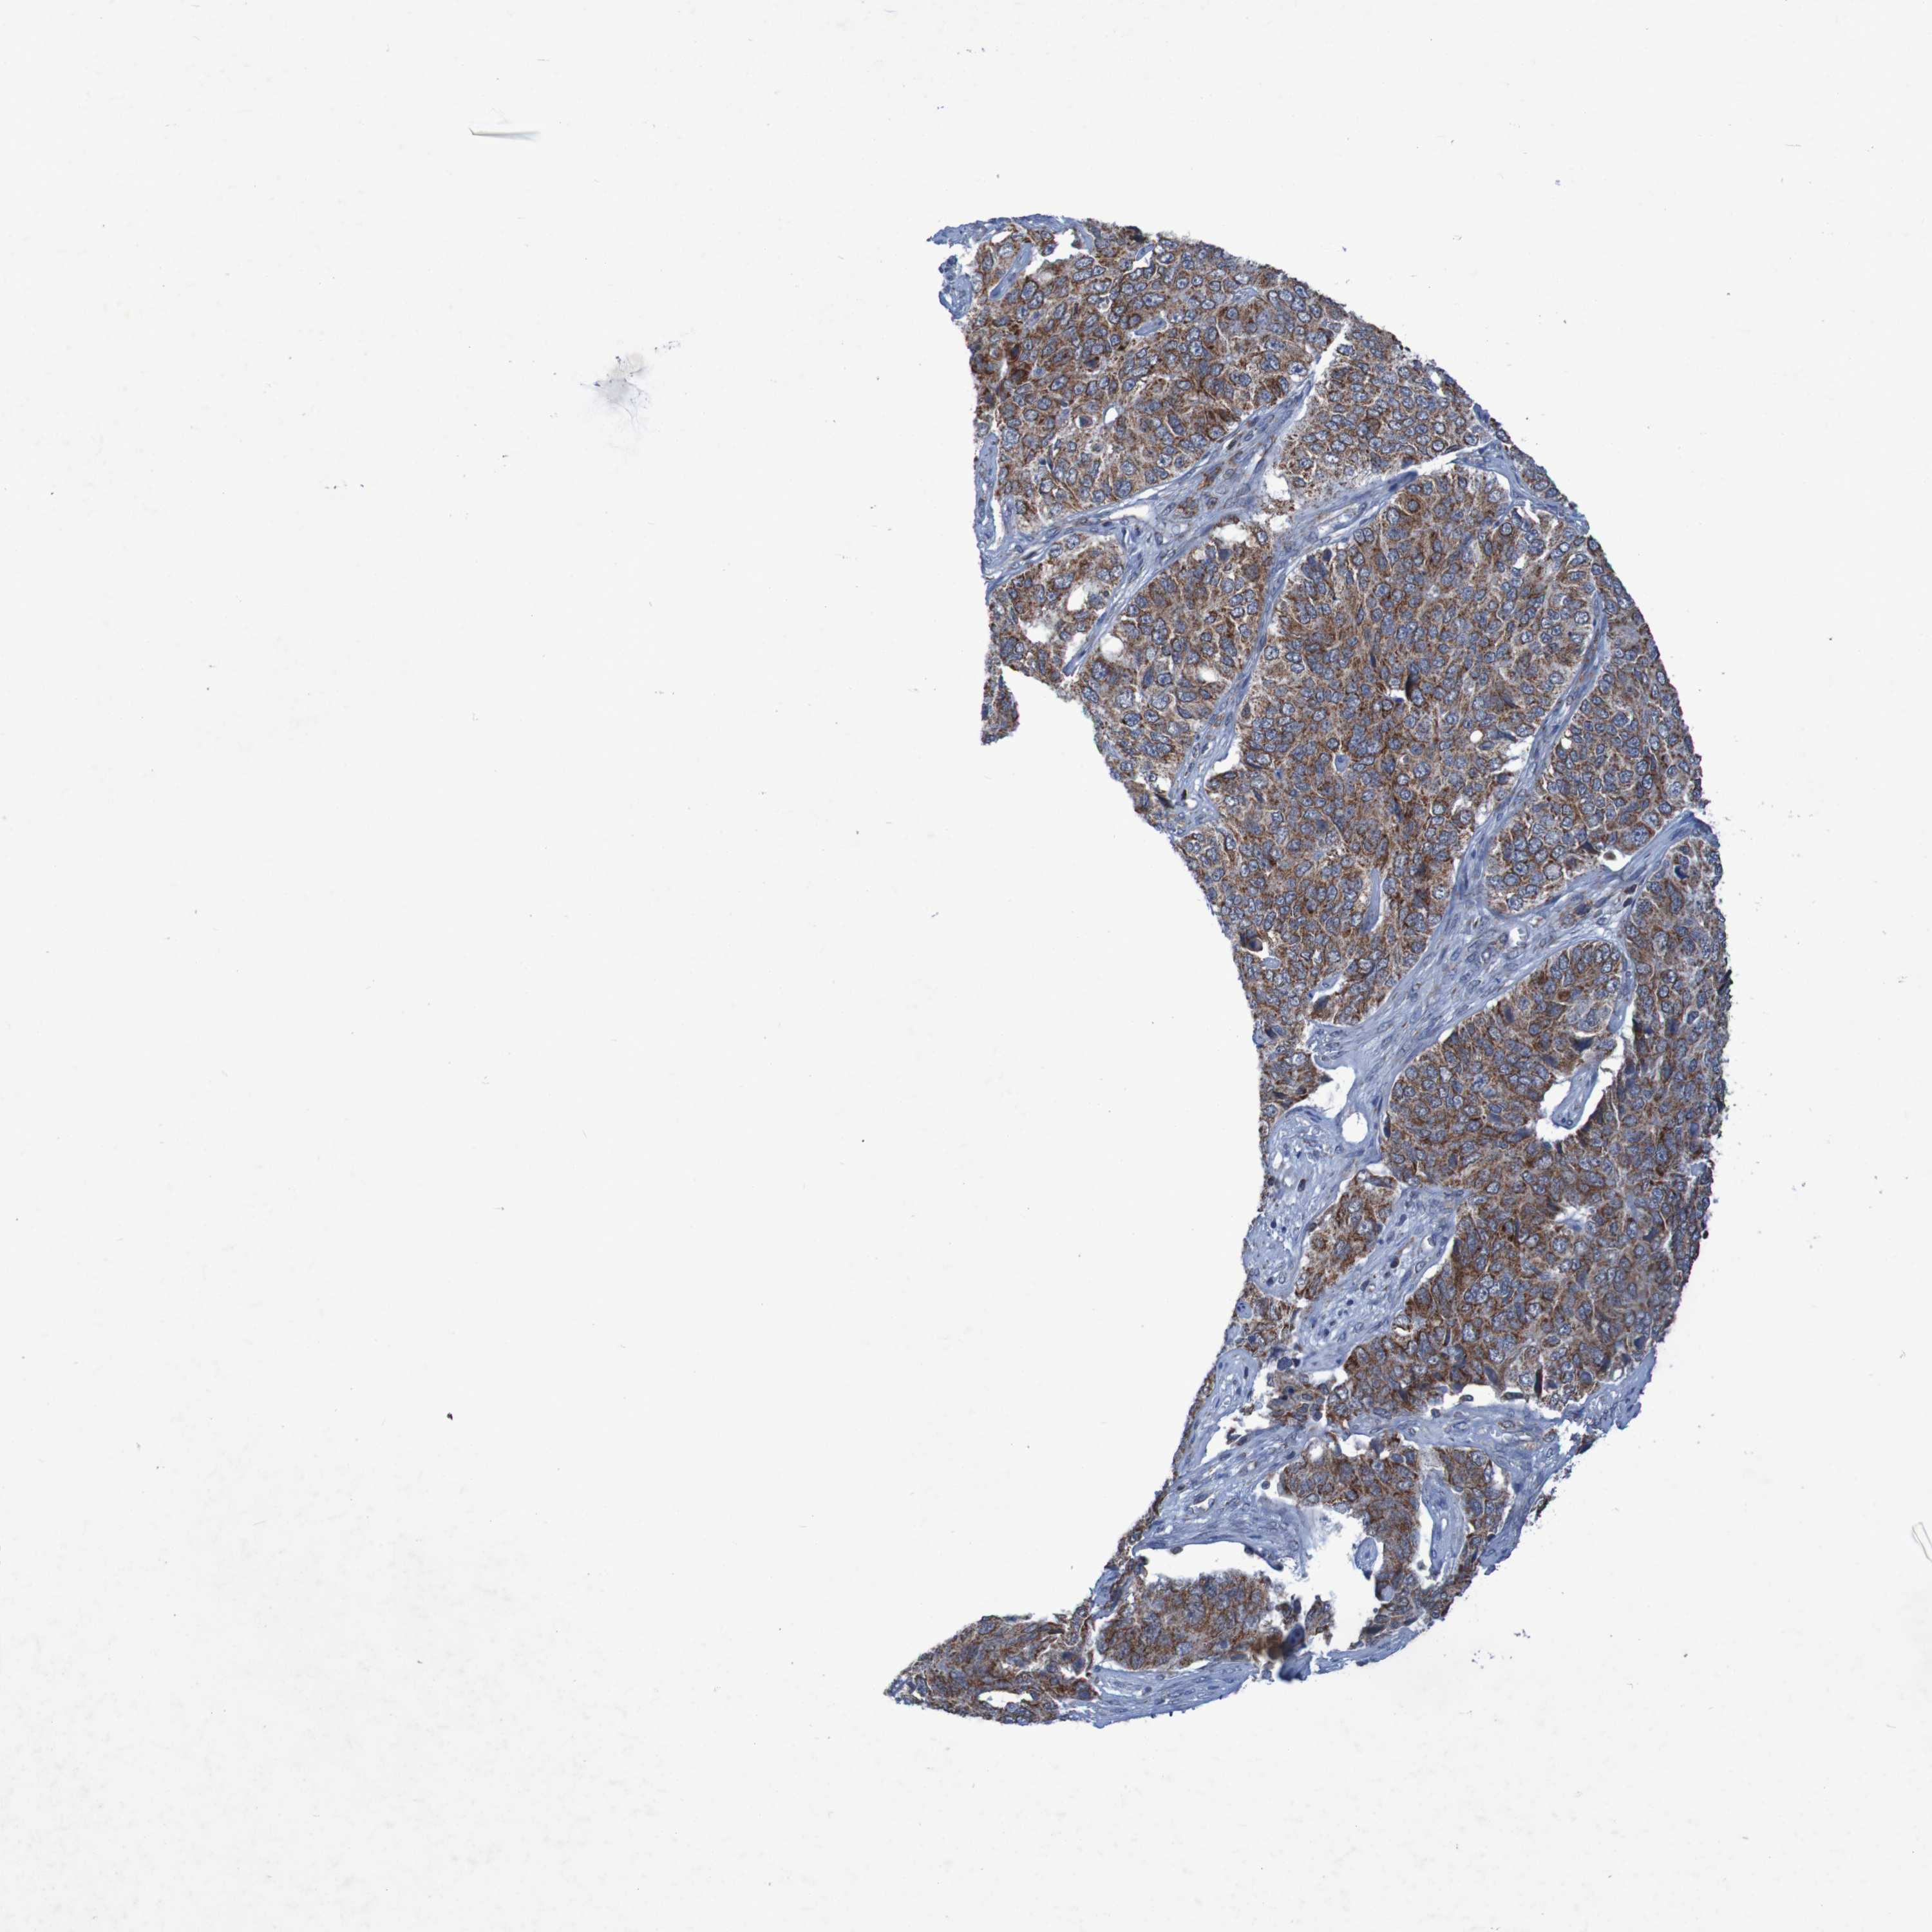

OVARIAN CANCER - Protein expressioni

A mouse-over function shows sample information and annotation data. Click on an image to view it in a full screen mode. Samples can be filtered based on level of antibody staining by selecting one or several of the following categories: high, medium, low and not detected. The assay and annotation is described here.

Note that samples used for immunohistochemistry by the Human Protein Atlas do not correspond to samples in the TCGA dataset.

Antibody stainingi

Antibody staining in the annotated cell types in the current human tissue is reported as not detected, low, medium, or high, based on conventional immunohistochemistry profiling in selected tissues. This score is based on the combination of the staining intensity and fraction of stained cells.

Each image is clickable and will lead to virtual microscopy that enables deeper exploration of all samples and also displays staining intensity scores, fraction scores and subcellular localization as well as patient and tissue information for each sample.

Antibody HPA010980

Antibody HPA011408

Staining

High

Medium

Low

Not detected

Intensity

Strong

Moderate

Weak

Negative

Quantity

>75%

75%-25%

<25%

None

Location

Nuclear

Cytoplasmic/membranous

Cytoplasmic/membranous,nuclear

Cystadenocarcinoma, serous, NOS